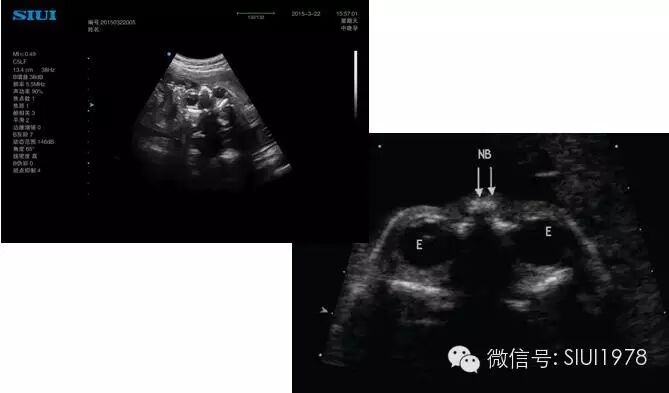

(三)经小脑横切面

1.扫查方法:在获得丘脑平面后声束略向尾侧旋转,即可获此切面。

2.判断标准:要求同时显示清晰的小脑半球且左右对称以及前方的透明隔腔,环状颅骨高回声左、 右对称,呈椭圆形。

3.主要观察的解剖结构及内容:

(1)环状颅骨高回声:完整的椭圆形环状颅骨高回声;

(2)小脑半球:在此切面上小脑半球呈对称的球形结构,最初为低回声,随着妊娠的进展其内部回声逐渐增强,晚孕期显示出一条条排列整齐的高回声线为小脑裂,两侧小脑中间有高回声的蚓部相连。蚓部的前方有第四脑室,后方有颅后窝池;

(3)脑中线:在此切面上脑中线居中,不连贯;

(4)透明隔腔:在脑中线的前1/3处,呈长方形的无回声区。透明隔腔位于两层透明隔之间,前部为胼胝体膝部,上方为胼胝体干,后为穹窿柱与胼胝体的汇合点,下方为胼胝体嘴部和穹窿体部。,位于两侧透明隔之间的腔隙即为透明隔腔,正常时不超过10mm;

(5)丘脑:,即丘脑。大脑及大脑外侧裂可清楚显示。

4.测量内容:测量小脑横径、 颅后窝池、 颈褶厚度。

5.临床意义:该切面是测量胎儿小脑横径、 颅后窝池、颈褶厚度的标准切面,常规检查此切面,可明显提高脊柱裂的检出率。很多颅脑异常在此切面上有明显表现,如无脑儿、脑膜脑膨出、柠檬头、胼胝体发育不良或缺失、前脑无裂畸形、蛛网膜囊肿、畸胎瘤、Dandy-Walker畸形、 颅窝后窝扩张、 颅后窝池消失、无脑回畸形、脑裂畸形、孔洞脑畸形、积水性无脑畸形、 脑白质软化等。